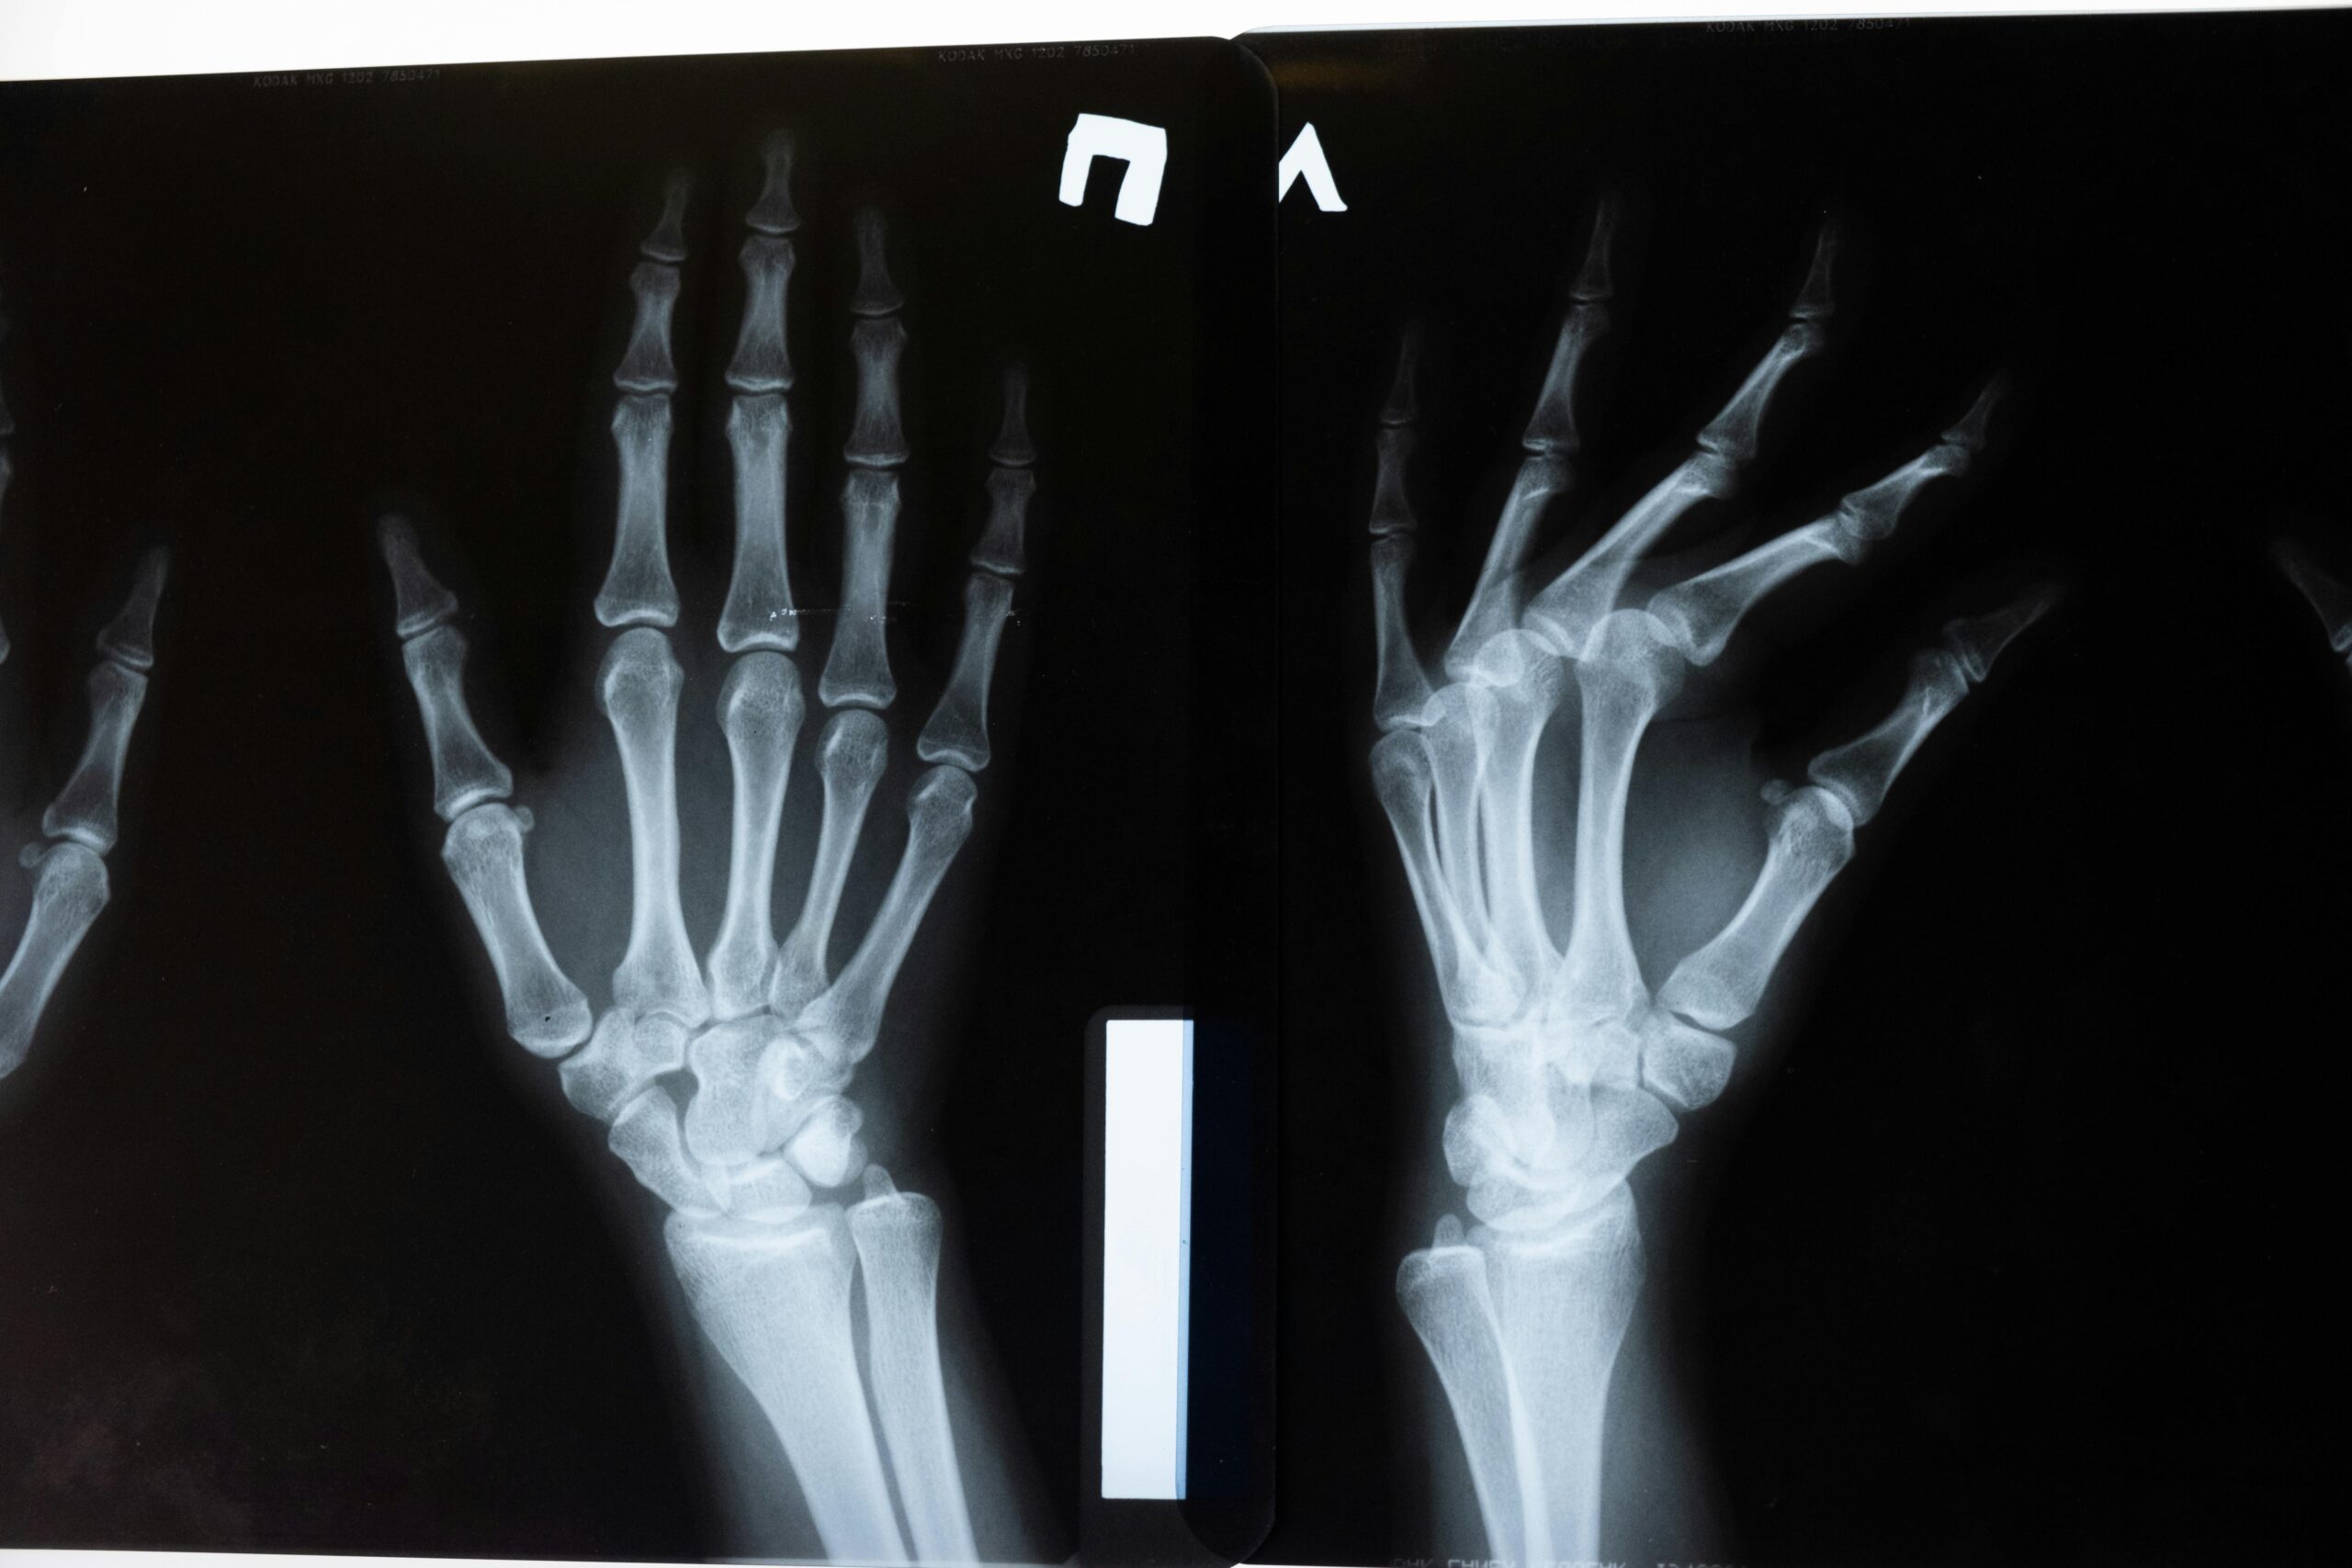

Diagnostic Imaging | x-ray

X-Rays are conveniently available at each of our clinics. Certified x-ray technicians stand ready to perform everything from chest to full body x-rays. Most x-rays can be taken, developed, and interpreted within minutes. Our X-Rays are digital and will become part of your electronic health record.